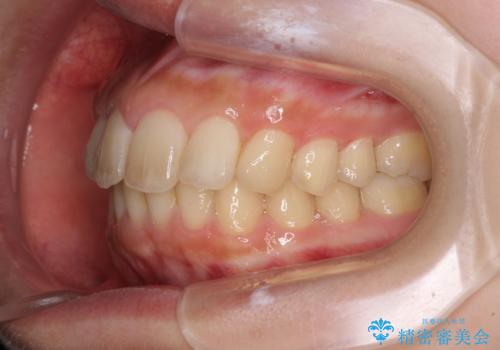

就職前にきれいな歯並びにしたい 大学生のインビザライン矯正

- 就職するまでに歯並びをきれいにしたいとのことで来院された患者様です。

前歯の叢生を気にしていましたが、極力突出感を改善できるようにすることとし、インビザラインにて矯正治療を行うこととしました。

改善の期待できない口元の突出感改善を希望されたため、いたずらに治療期間が延びましたが、きっちりと仕上がりました。